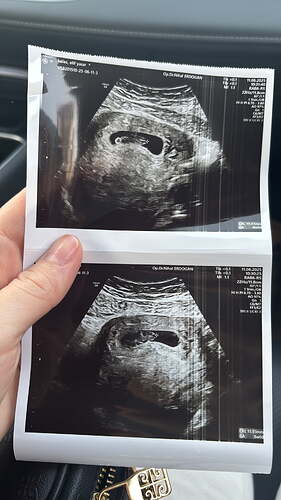

Kız bebiş kesesi gibi ![]()

Yok canım karıştırma ikinciye hamileyim![]()

Erkek bebiş kesesi gibi ![]()

Oğlum 14 aylık karnımdaki 1 aylık aralarında 2 yaş sayılır

Bence kız nett